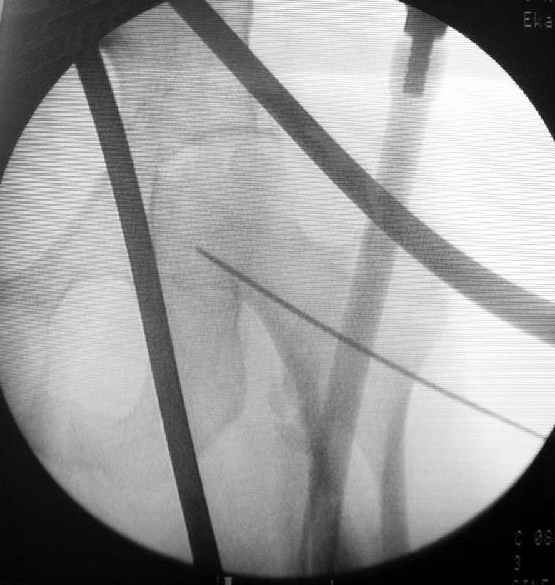

Как раз недавно у меня был примерный случай: больному 36 лет, поступил ночью, травма в результате мотоциклетной аварии, кроме чрезвертельного и спирального перелома левого бедра имеется переломы костей предплечья с этой же стороны. Скелетное вытяжение, а на следующий день больной про оперирован на ортопедическом столе с дистракцией. Чтобы не расколоть чрезвертельный перелом провели временную спицу ближе к переднему кортексу, из малого разреза костодержатель для репозиции, а фиксацию провели антиградным штифтом. Этапы операции на снимках.